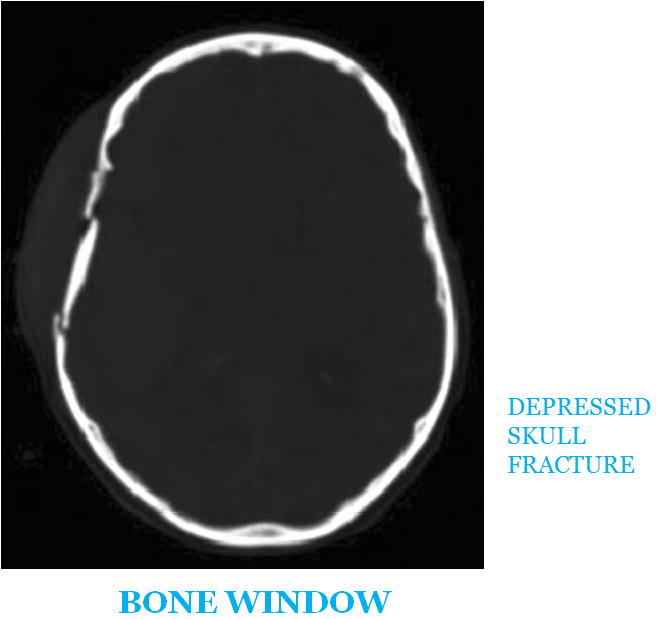

DEPRESSED SKULL FRACTURE | Buyxraysonline